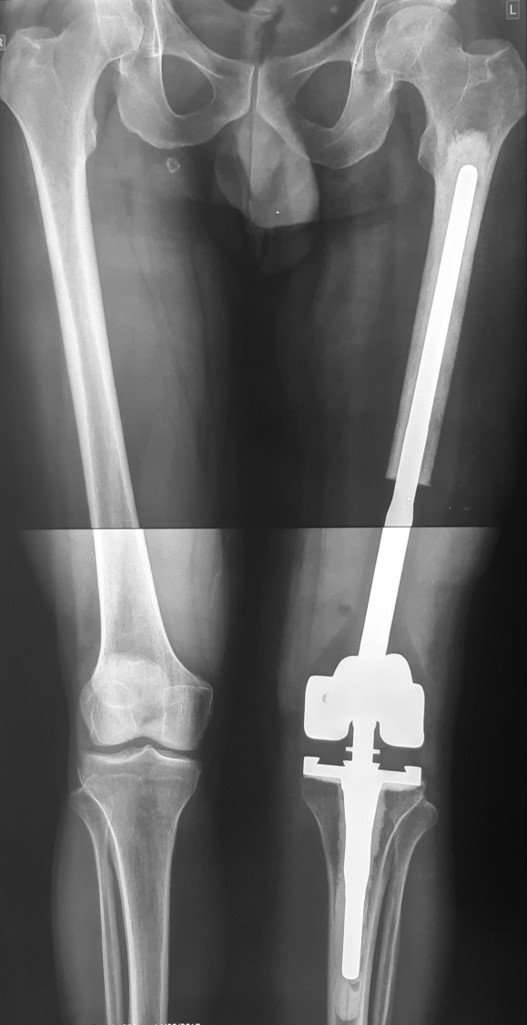

2. Остеосаркома большеберцовой кости

После получения предоперационной химиотерапии в МЦ ''Наири" была проведена органосохраняющая операции – сегментарная резекция верхней трети большеберцовой кости и коленного сустава, замещение образовавшегося костно-суставного дефекта индивидуальным, изготовленным на заказ эндопротезом. В послеоперационном периоде пациент продолжил показанную по протоколам химиотерапию. В настоящее время лечение завершено, признаков прогрессирования заболевания нет, оперированная конечность функционально пригодная, опороспособность полная.

После операции